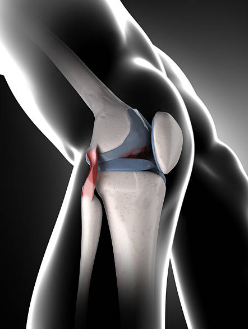

1. 내측 인대 손상

내측 인대는 무릎 안쪽에 있는 인대로, 무릎을 안정시키고 관절의 움직임을 조절하는 역할을 합니다. 내측 인대가 늘어나거나 찢어지면 무릎 안쪽 통증이 발생하며, 부기, 멍, 무릎의 불안정감 등의 증상이 동반될 수 있습니다. 내측 인대 손상은 스포츠 활동 중에 다리를 외반시키거나 무릎을 과도하게 굽히는 경우에 자주 발생합니다.